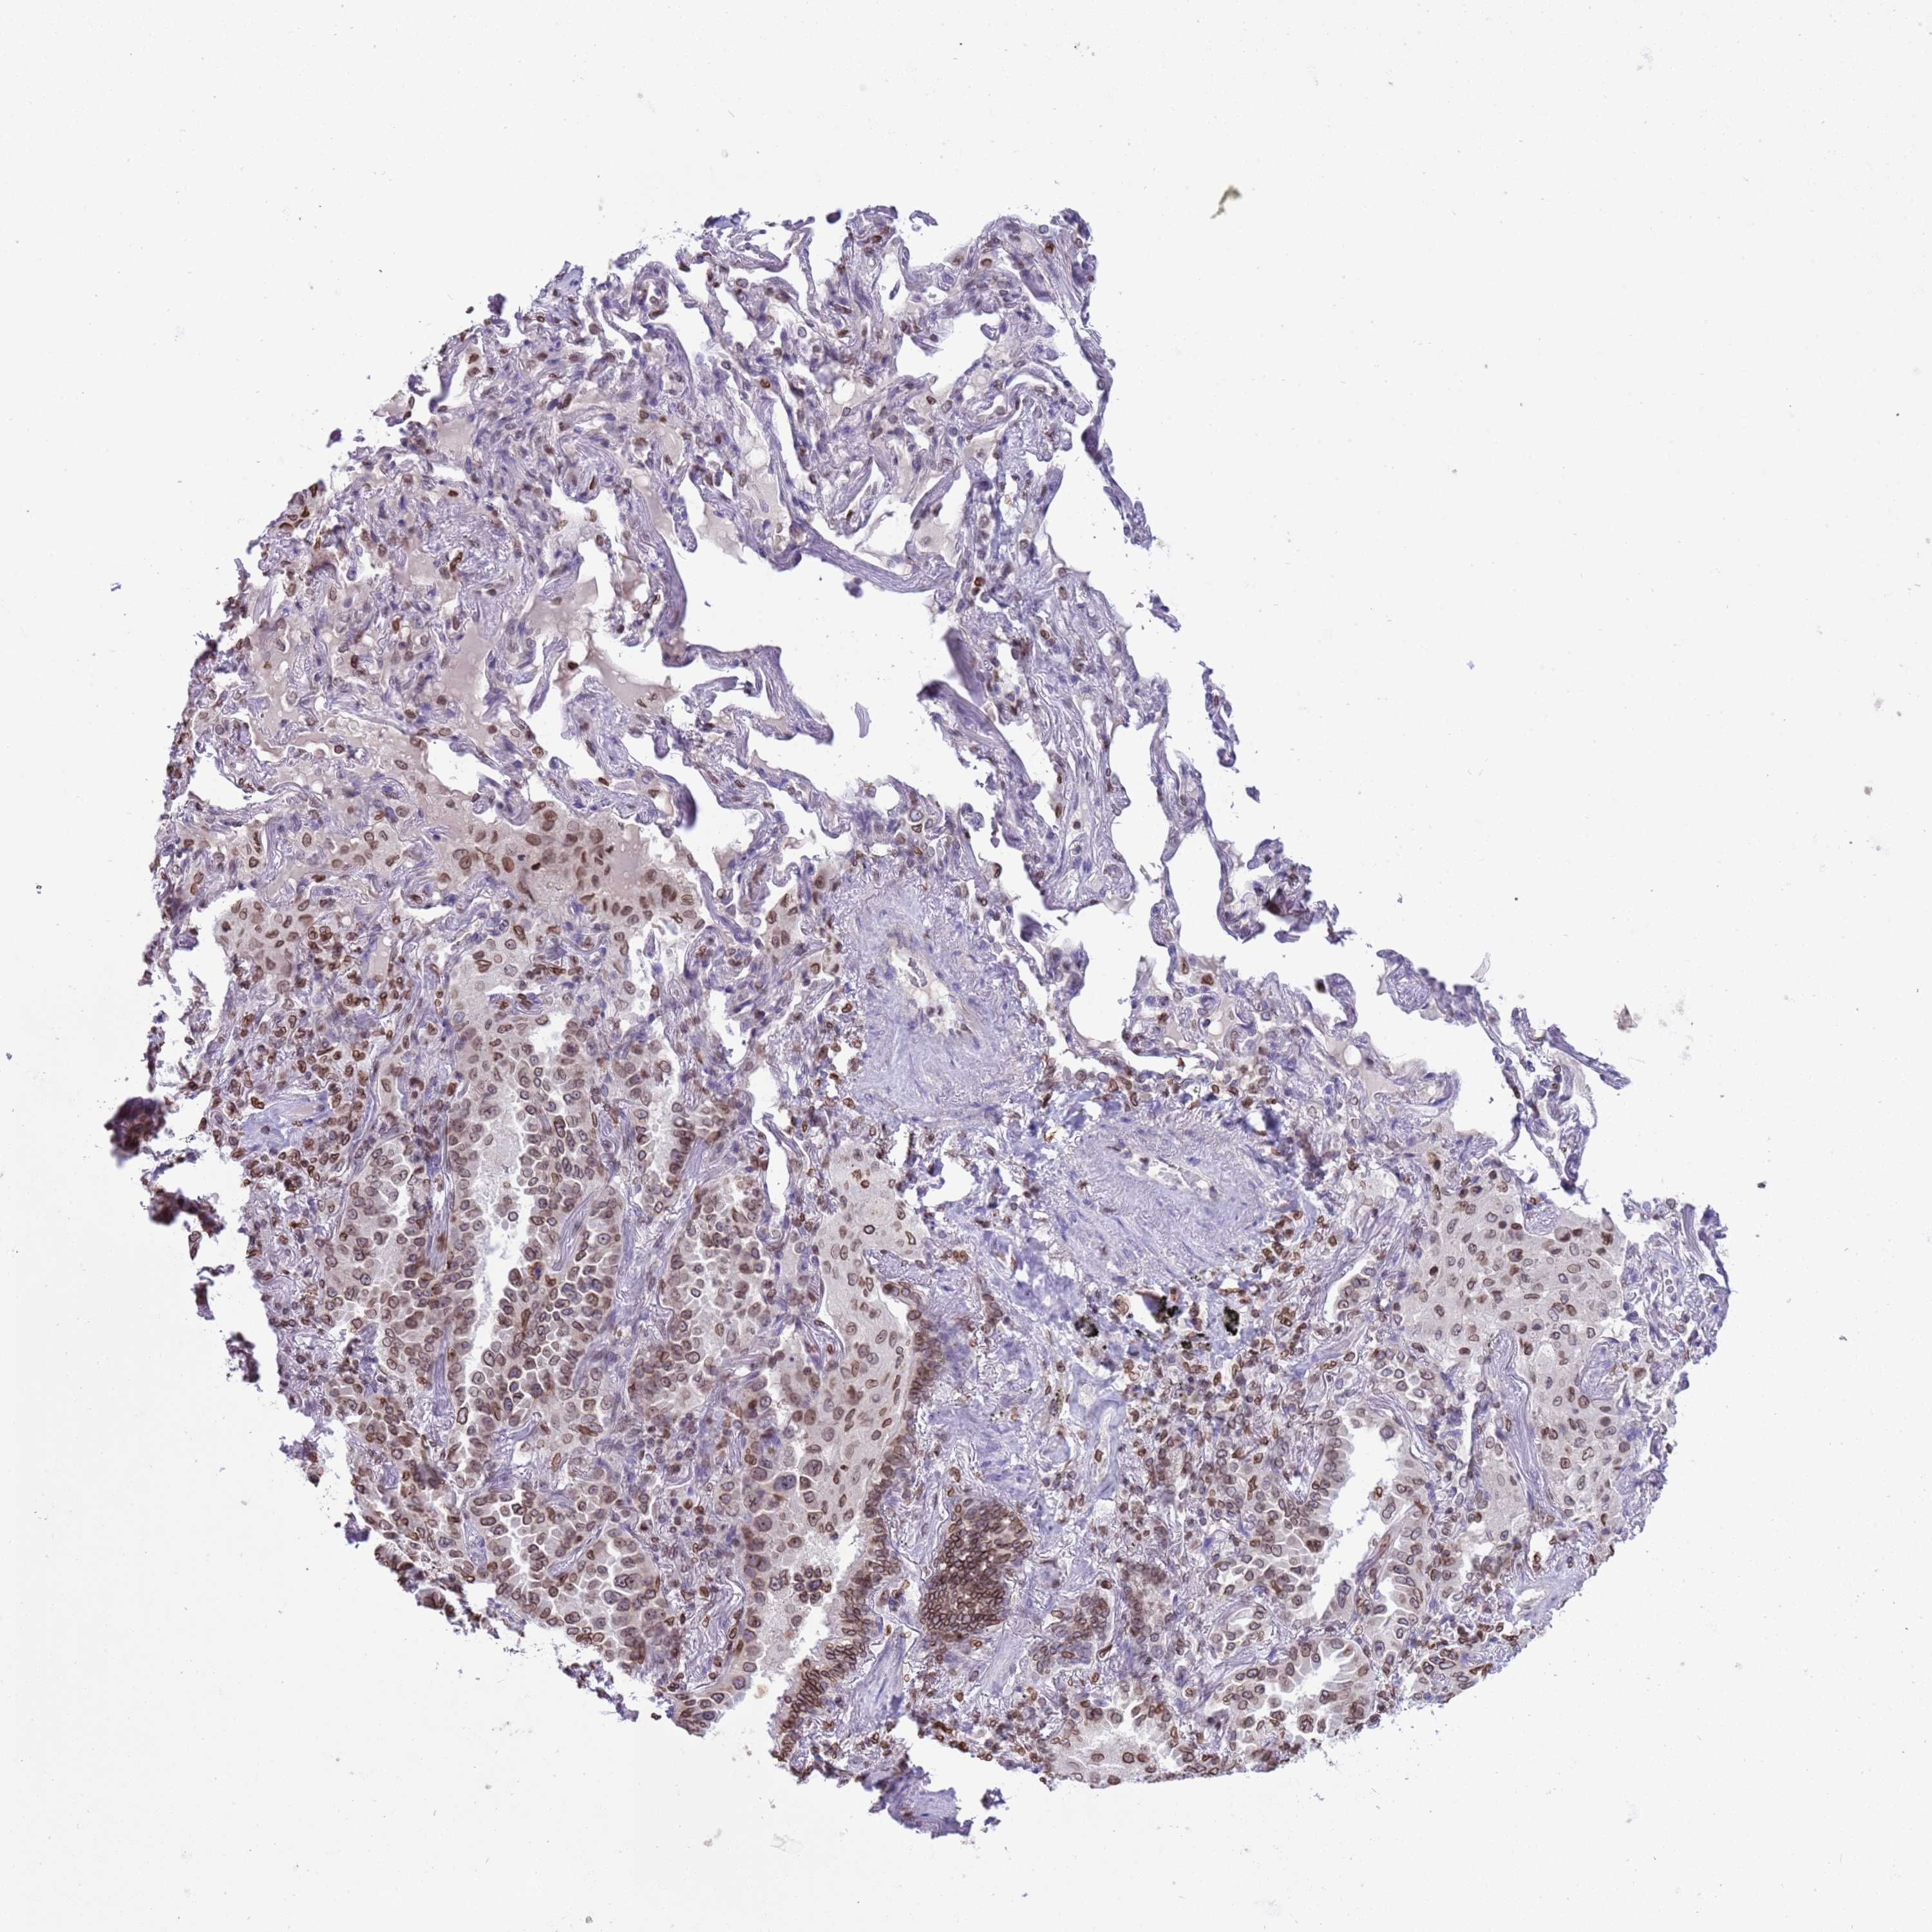

LUNG SQUAMOUS CELL CARCINOMA (TCGA) - Interactive survival scatter ploti

The Survival Scatter plot shows the clinical status (i.e. dead or alive) for all individuals in the patient cohort, based on the same data that underlies the corresponding Kaplan-Meier plots. Patients that are alive at last time for follow-up are shown in blue and patients who have died during the study are shown in red.

The x-axis shows the expression levels (FPKM) of the investigated gene in the tumor tissue at the time of diagnosis. The y-axis shows the follow-up time after diagnosis (years). Both axes are complimented with kernel density curves demonstrating the data density over the axes. The top density plot shows the expression levels (FPKM) distribution among dead (red) and alive patients (blue). The right density plot shows the data density of the survived years of dead patients with high and low expression levels respectively, stratified using the cutoff indicated by the vertical dashed line through the Survival Scatter plot. This cutoff is automatically defined based on the FPKM cutoff that minimizes the p-score. The cutoff can be changed by dragging the vertical line or by entering a cutoff value in the square labeled "Current cut-off".

Under the Survival Scatter plot the p-score landscape (black curve; left axis) is shown together with dead median separation (red curve; right axis). Dead median separation is the difference in median mRNA expression between patients who have died with high and low expression, respectively. It is calculated as follows: median FPKM expression of dead patients with high expression - median FPKM expression of dead patients with low expression. This is intended to aid the user in visually exploring custom cutoffs and the associated p-scores and dead median separation.

Individual patient data is displayed and can be filtered by clicking on one or more of the category buttons on the top of the page. Categories describing expression level and patient information include: high, low, alive, dead, female, male and tumor stages. The scale of the x-axis can be toggled between linear and log-scale by clicking on the "x log" button. Mouse-over function shows TCGA ID, patient information and mRNA expression (FPKM) for each patient.

& Survival analysisi

Kaplan-Meier plots summarize results from analysis of correlation between mRNA expression level and patient survival. Patients were divided based on level of expression into one of the two groups "low" (under cut off) or "high" (over cut off). X-axis shows time for survival (years) and y-axis shows the probability of survival, where 1.0 corresponds to 100 percent.

DHX37 is not prognostic in Lung Squamous Cell Carcinoma (TCGA)

: 12.54

Average pTPM 9.8

Number of samples 489